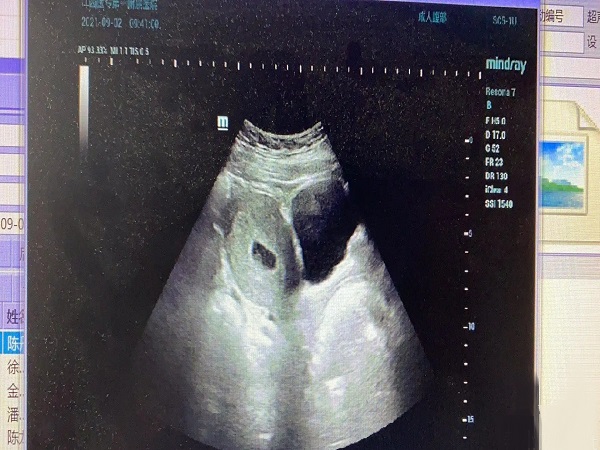

hcg翻倍不好未见孕囊的情况其实是比较复杂的,可能是胚胎发育异常导致的,也有可能是已经生化妊娠了,另外也不能够排除宫外孕的可能。但是不管怎么样这种情况都属于异常,需要进行进一步的检查来了解具体的情况,方便医生进行判断和治疗。下面就为大家详细介绍一下hcg翻倍不好未见孕囊的原因,感兴趣的朋友可以详细了解一下。

1胚胎发育异常:正常情况下在女性怀孕30-40天的时候就会出现孕囊,并且hcg也会呈现出翻倍增长的情况,如果hcg增长缓慢并且检查没有孕囊的话,很可能就是胚胎发育缓慢或者异常所导致的; 2生化妊娠:如果孕初期hcg翻倍不好并且在宫内也没有看见孕囊的话,就很可能是胚胎已经生化妊娠了,需要进行进一步的检查; 3宫外孕:如果女性是宫外孕的话,那么也会出现hcg增长异常并且B超检查宫内看不见孕囊的情况,需要结合B超检查来确定。

hcg翻倍不好未见孕囊正不正常